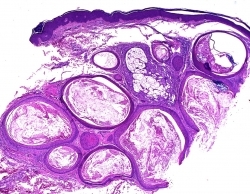

What is this neoplasm?

1 Trichoadenoma

2 Trichoblastoma

3 Trichoepithelioma

4 Basal cell carcinoma

5 Nevus comedonicus

Trichoadenoma

Trichoadenoma: A nodule on the face or butt that is slightly depressed. Typically confined to the upper dermis and composed of multiple milia or infundibular-like cysts that have a squamous epithelial lining associated with a granular layer and central flakey keratin in the lumen. The stroma can be sclerotic. The lesion is composed primary of cysts with a few thin strands of basaloid cells; if basaloid strands predominate with only a few cysts then lesion is a trichoepithelioma.